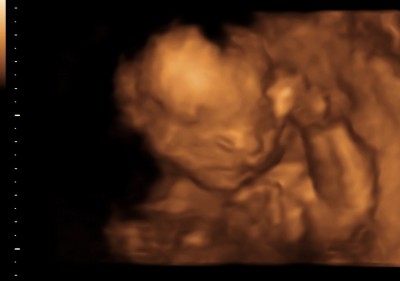

Resimliii bilgisi olan varmı

Cinsiyet tahmininde bulunabilirmisiniz

Görür görmez erkek geldi içimden

Valla benim içimden erkek geldi canım

Kuzum bu ultrason fotoları normal bedeniyle olan halı biri yan Durmuş digeride yüzü burdan anlaşılmaz özel bölgesine bakıldığında üç çizgi varsa kız oluyor iki çizgi varsa erkek

Bence erkek icime oyle dogdu

Bende erkek hissttimm hayırla gelsin inşallah